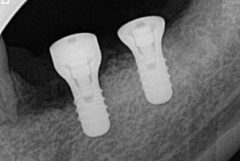

インプラントの埋入を終えました。

![]()

前後の被せものを戻して撮影しています。